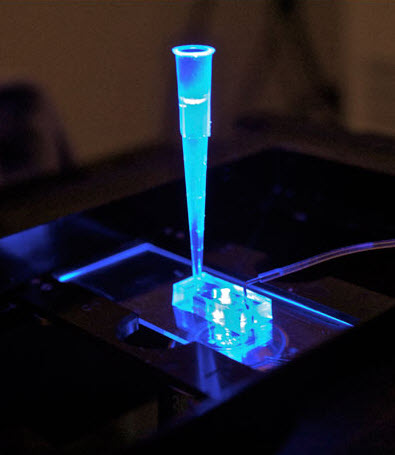

‘Heart on a chip’ reduces time and cost in drug testing for safety and efficacy

Replaces animal models, which have a high failure rate in predicting human reactions to new drugs